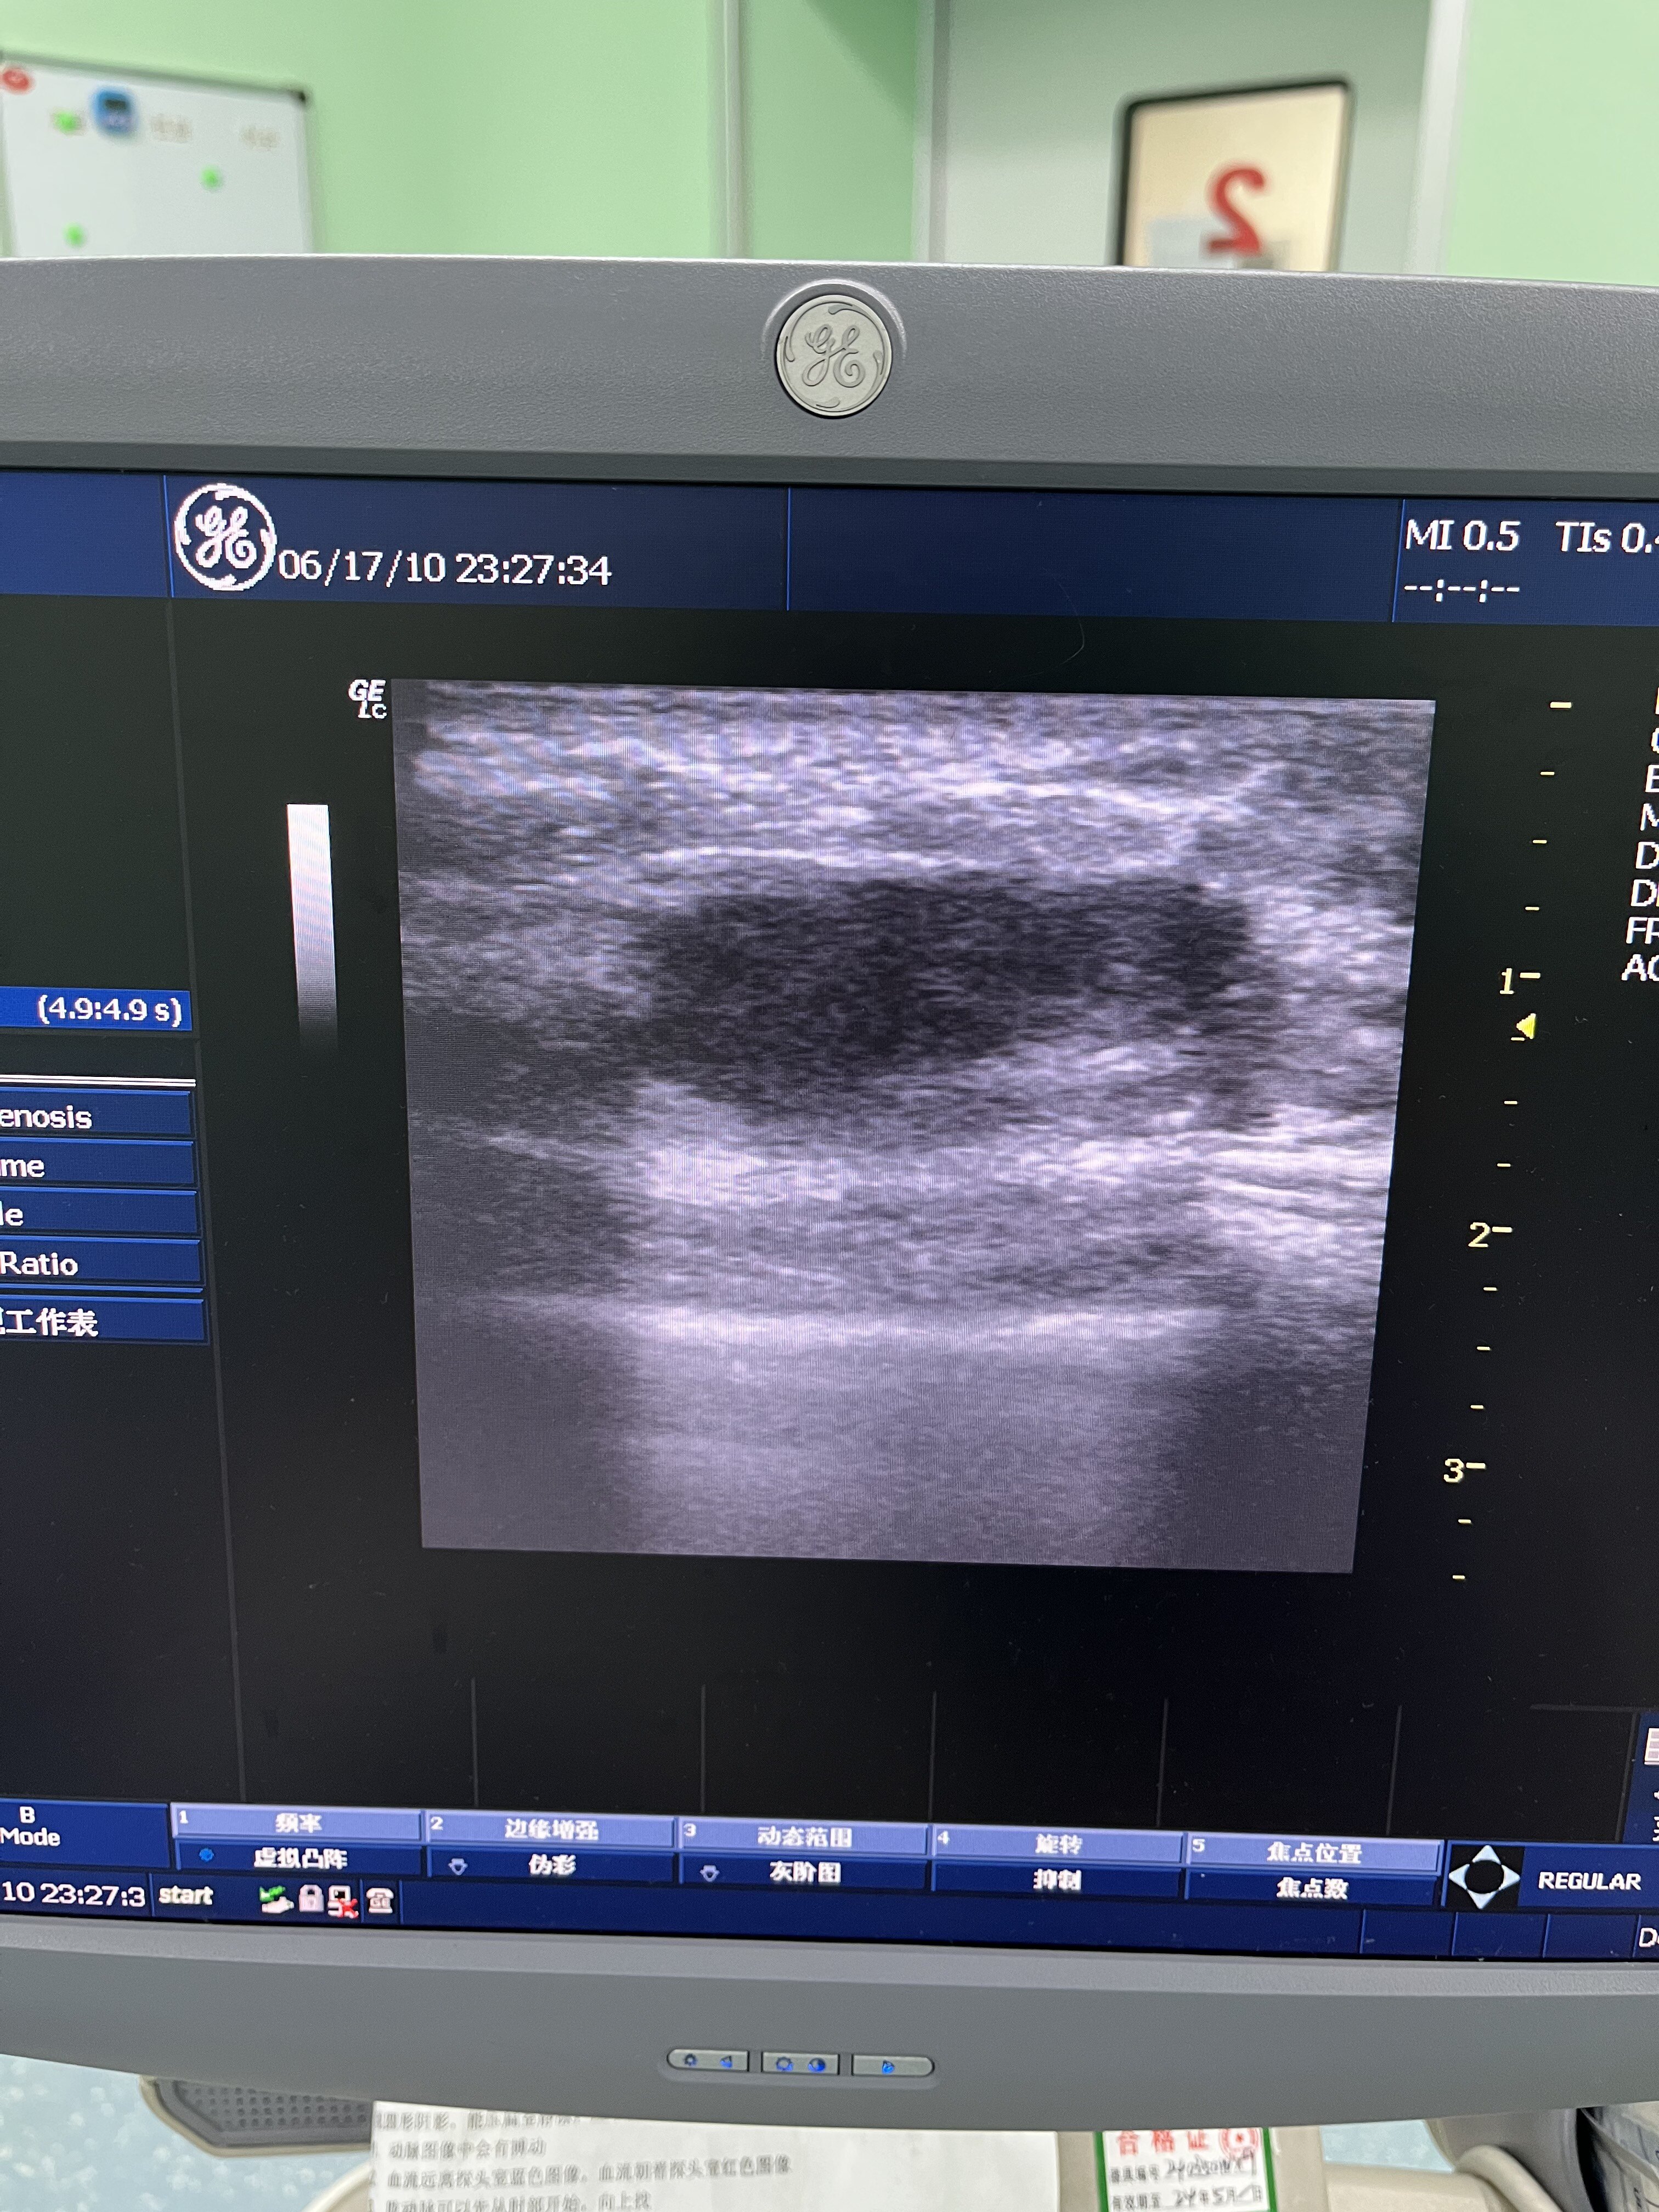

近來,雖然暑假臨近尾聲,但還有一些學生,不得不來醫(yī)院診治。有一個14歲女孩,升初二,因為一側(cè)乳腺無緣無故的腫起來,來門診就診,我檢查后發(fā)現(xiàn),雖然不紅不疼,稍微有點腫,但深部有一個腫塊,3厘米左右。而且小女孩有先天性乳頭凹陷,容易藏污垢,夏天出汗后引起炎癥,診斷為乳腺膿腫。手術(shù)中切除了包塊,而且糾正了乳頭凹陷,外形更好了

現(xiàn)在乳腺腫塊的發(fā)病率非常高,普查會發(fā)現(xiàn),很多女性都有乳腺腫塊,讓大家非常擔心焦慮,那腫塊需不需要手術(shù),主要看以下幾個方面,一,腫塊的大小,假如腫塊大于1厘米,那建議盡早手術(shù)。如果腫塊小于1厘米,邊緣不規(guī)則,也肯定需要手術(shù)。二,看腫塊有沒有包膜,這在超聲上看比較明顯,一般良性腫塊有包膜,邊界清楚。三,腫塊在定期復查的過程中,有生長的趨勢,肯定要手術(shù)。 那如何選擇手術(shù)方式呢,我在十幾年臨床經(jīng)驗中總結(jié),微創(chuàng)手術(shù)雖然恢復快,沒有疤痕,但是主要適用腫塊比較小的,最好小于2厘米,大的腫塊比較容易切不干凈,有殘留。大于2厘米的,還是做傳統(tǒng)切除手術(shù)比較好。